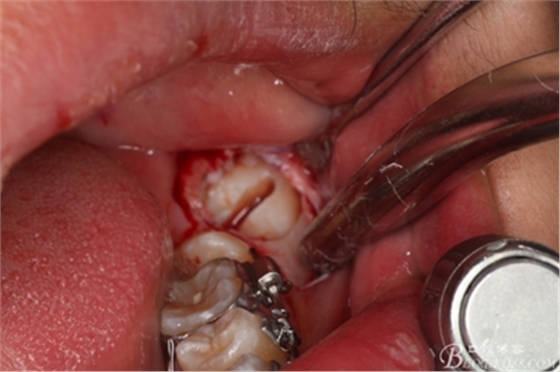

圖12.縱分完成的牙冠

圖13.牙挺放入分開的牙縫之間

圖14.先取出遠(yuǎn)中部分。